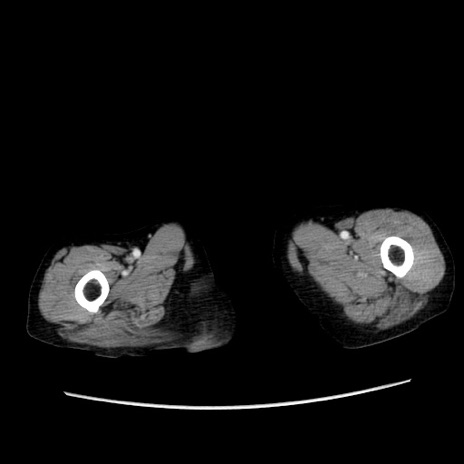

症例25(横断像)

症例

【症例】80歳代女性

【主訴】胸のつかえ感

【現病歴】約9時間前に食後から胸のつかえた感じあり、嘔吐あり、来院。

【既往歴】胃癌(全摘)、胆摘、虫垂炎

【身体所見】心窩部に圧痛あり、反跳痛なし。

【データ】WBC 5700、CRP 0.05